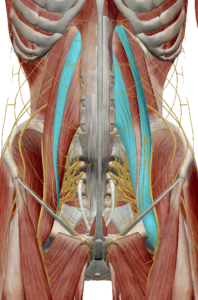

(1) 대요근과 소요근(왼쪽 소요근, 오른쪽 대요근)

요추에 직접 연결된 대요근과 소요근입니다.

대요근은 골반이 아닌 대퇴골에 붙어 고관절 움직임에 직접 관여합니다.

대요근이 수축하면 요추의 신전 또는 고관절 굴곡 움직임이 발생합니다.

소요근은 치골에 붙어 골반 움직임에 관여합니다.

소요근이 수축하면 요추의 신전 또는 골반의 후방 경사가 발생합니다.